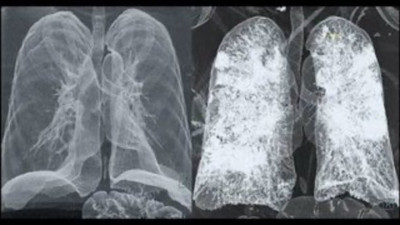

Koronavirüsün akciğere verdiği zarar görüntülendi! Koronavirüs’ten ölen bir hastanın akciğer röntgeni ve tomografisi, virüsün akciğerlere verdiği zararı gözler önüne serdi.

Corona virüsün insan vücudundaki etkisi böyle görüntülendi! Corona virüs nedeniyle hayatını kaybeden Çin vatandaşının röntgen filmleri ortaya çıktı. Filmlerde ölümcül virüsün insanların akciğerlerinde nasıl etki yarattığını gözler önüne serdi.

Coronavirüsün akciğerde nasıl yayıldığı görüntülendi Çinli doktorlar, 2019-n?V Coronavirüsü bulaşan bir hastanın akciğerlerini gösterdi.